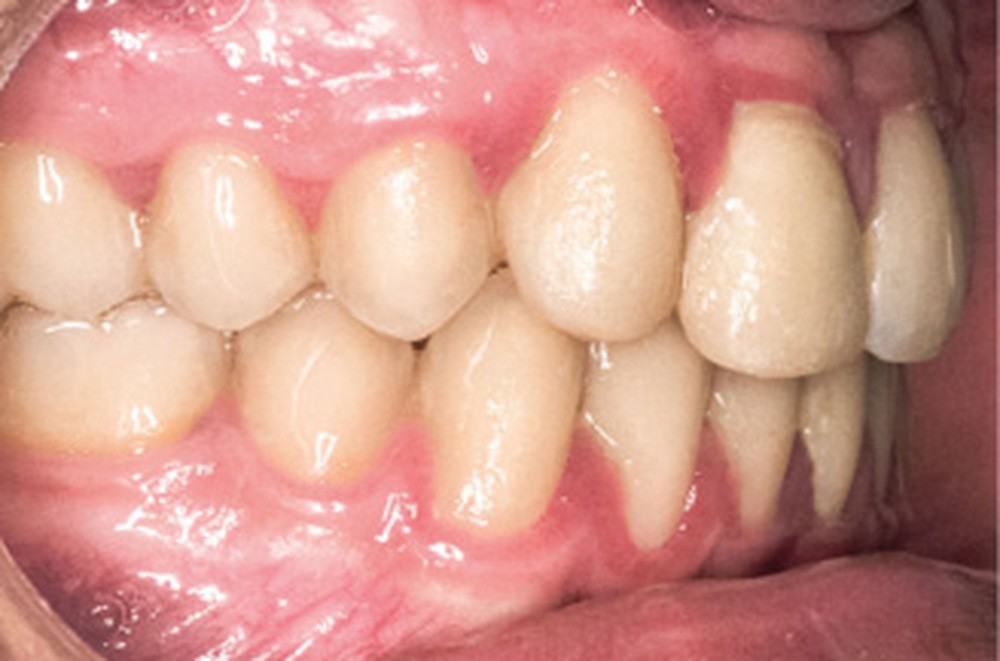

D’un point de vue occlusal, le patient, en denture adulte jeune stable, présente une classe II d’Angle bilatérale de 4 mm, associée à un encombrement maxillaire de 5 mm et mandibulaire de 2 mm. La face mésiale de 21 est centrée avec le plan sagittal médian, la non-concordance des médianes incisives est d’origine mandibulaire (déviation de la médiane mandibulaire vers la gauche) (fig. 1b-d).

La gestion occlusale de la substitution est primordiale [2] : 12 a été centrée dans l’espace dévolu à la 11 de façon à réaliser une facette pour augmenter son diamètre mésio-distal ; la pointe cuspidienne de 13 a été meulée et du torque radiculo-palatin a été ajouté de façon à diminuer le bombé radiculaire. 14 joue le rôle d’une canine : l’ajout de torque radiculo-vestibulaire a une double action, à la fois esthétique, pour créer une bosse canine, et fonctionnelle pour ingresser la cuspide palatine, permettant les mouvements de latéralités sans interférences.

En ce qui concerne les objectifs de traitement, le profil du patient reste pratiquement inchangé avec une compétence labiale au repos (fig. 4a). D’un point de vue occlusal, la correction en classe I d’Angle est obtenue (fig. 4b-c). La difficulté résidait dans la gestion de la substitution (fig. 5) ; outre le manque d’hygiène notable due à une perte de motivation du patient sur la fin de traitement, notons une perte d’alignement de la ligne des collets en regard de 13, ainsi qu’une bosse canine toujours présente. Une correction par chirurgie parodontale permettra la symétrie du sourire et l’intégration prothétique optimale de la restauration de 11 [3] (fig. 6).